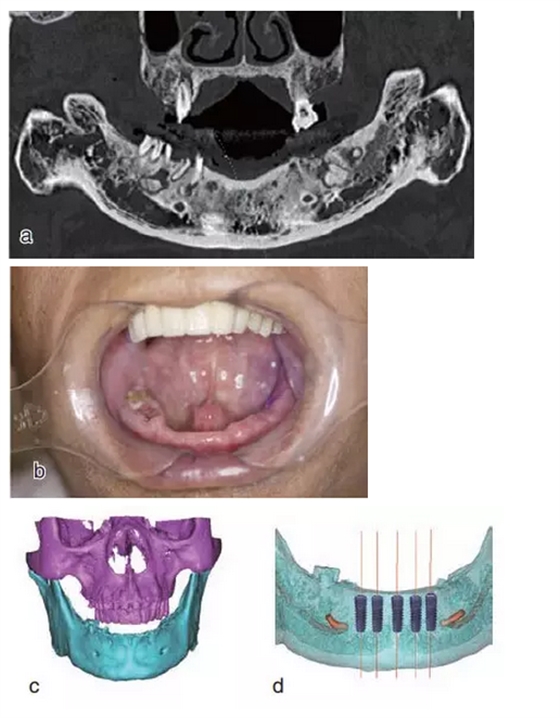

術(shù)前拍攝錐形束CT,進(jìn)行三維重建和種植方案規(guī)劃。從CT圖像中可以看出頜骨內(nèi)有骨島和殘根,為避免種植體植入骨島區(qū),考慮在兩側(cè)頦孔區(qū)種植4~5顆種植體,采用套筒冠進(jìn)行即刻修復(fù)。從重建的結(jié)果中可知前牙區(qū)牙槽嵴呈刀刃狀。種植方案為:對前牙區(qū)牙槽嵴進(jìn)行截骨修整,并在兩頦孔之間的區(qū)域內(nèi)植入5顆種植體。

圖15

種植方案的規(guī)劃:a.患者的CT圖像的截面圖,圈紅處為骨島;b.患者摘掉活動義齒后的下頜;c.患者上下頜骨的CT三維重建;d.下頜骨截骨后模擬植入5顆種植體